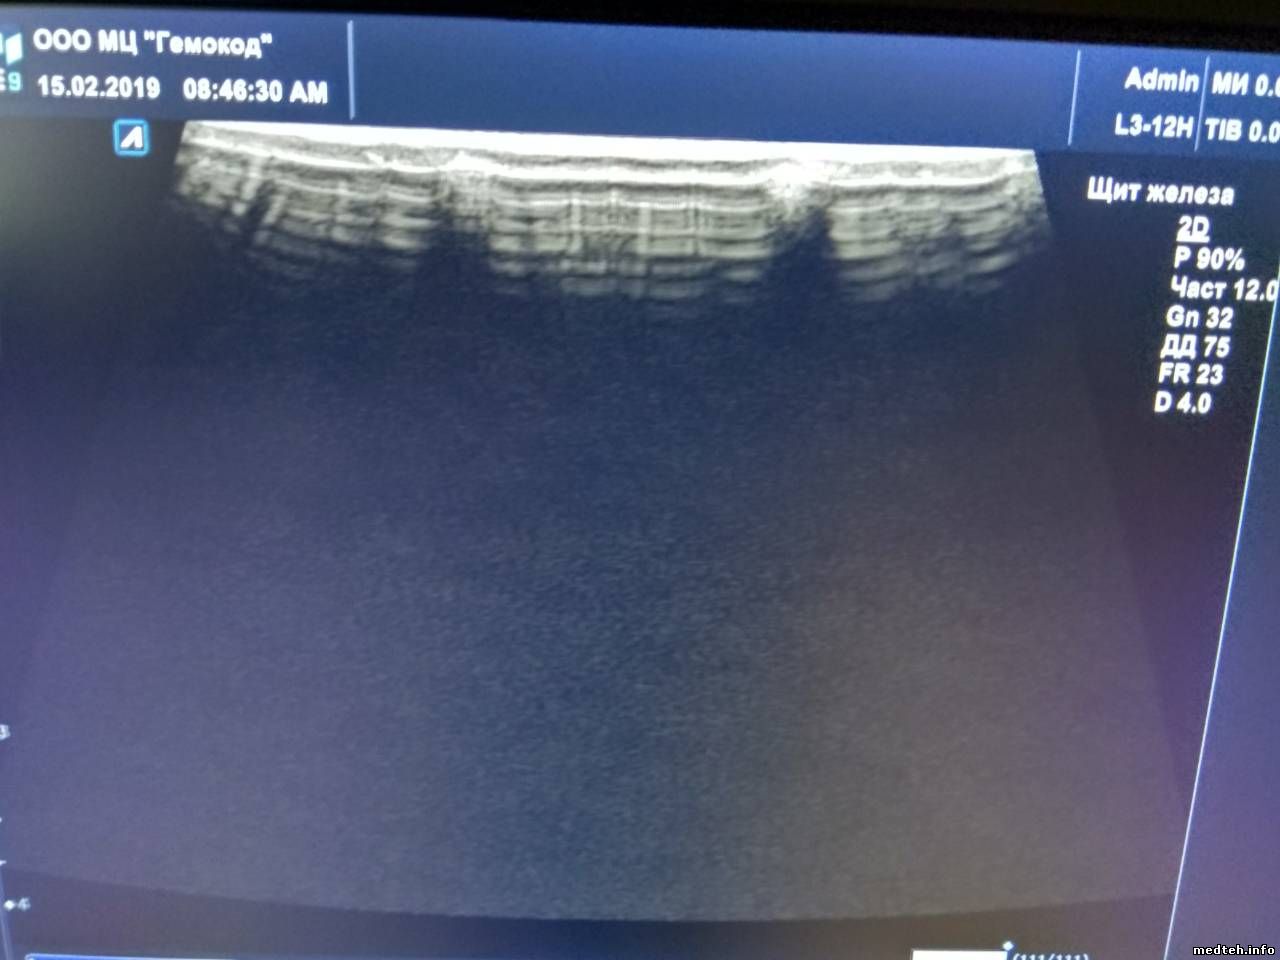

Добрый день! Уважаемые коллеги, посоветуйте,плиз..Что можно сделать в данной ситуации? Замена линзы? И если исправит проблему, то кто может взяться за это? Соответственно, сроки ремонта,цена,гарантия на работу? Сам ни разу такое не делал и опасаюсь...

Фото прилагаю..

2007676.jpg (50.8 Kb) · 1106821.jpg (50.8 Kb) · 6863907.jpg (127.3 Kb) · 2895305.jpg (127.3 Kb) · 5262964.jpg (88.9 Kb) · 5110581.jpg (62.2 Kb)

pilot9275Дата: Пятница, 15.Фев.2019, 09:36 | Сообщение # 432

Чебоксары

женек 75